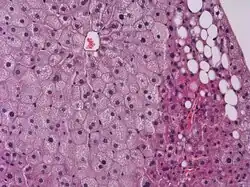

![]() Fotografía microscópica mostrando un Hígado graso (esteatosis macrovesicular), como se ve en una esteatohepatitis no alcohólica. Tinción tricrómica. | ||

Se produce hepatomegalia (aumento del tamaño del hígado) y el hígado adopta un aspecto moteado y blando. Al microscopio óptico se observa como los hepatocitos muestran gotas lipídicas que pueden ser de gran tamaño y existir pocas (célula en anillo de sello, más característico de situaciones crónicas) o ser pequeñas y abundantes (célula espumosa, más típico de situaciones agudas). La acumulación de triacilglicéridos en unas u otras zonas del lobulillo hepático dependerá de la causa: en la congestión hepática (que genera isquemia) los triglicéridos se acumulan preferentemente en el centro del lobulillo (esteatosis centrolobulillar) tal y como ocurre en la insuficiencia cardíaca, alcoholismo, etc. La esteatosis perilobulillar es producida tras períodos prolongados de ayuno. Si estos procesos se acompañan de hepatitis (esteatohepatitis) se acaba produciendo necrosis que desembocará en fibrosis hepática. El hígado graso suele aparecer a causa de la toma de grandes medidas de alcohol, azúcares o grasas.